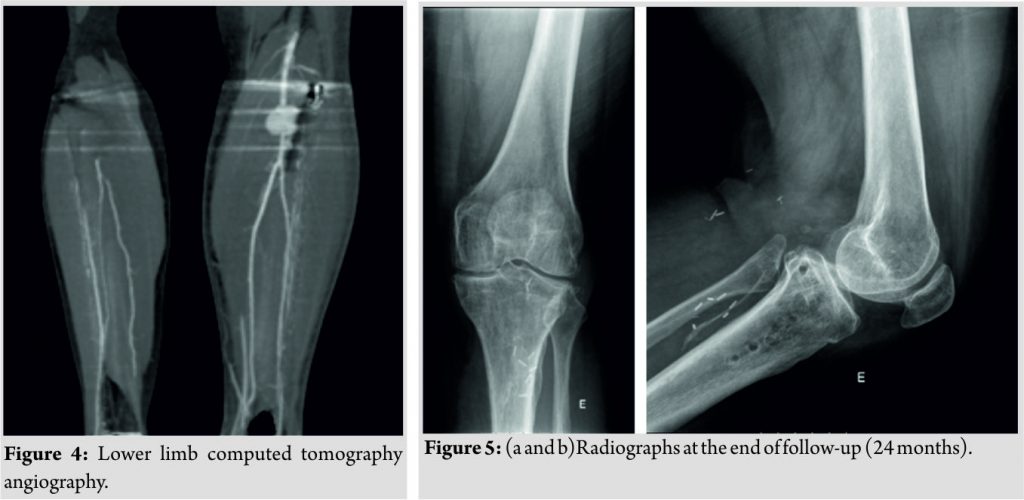

A suction drain was used but the tourniquet was not released before wound closure, as that was not standard practice in our institution. On the 1st post-operative day, the patient presented with an active ankle dorsiflexion deficit but maintained active toe flexion and extension and showed no neurologic deficits. The capillary refill time was <2 s, and he had palpable distal pulses. The suction drain had collected 650 cc of hematic fluid. He was diagnosed with partial common peroneal nerve palsy, and a Boxia-type ankle-footorthosis (AFO) was applied. On the 7th post-operative day, the patient complained of increasing pain and edema in is leg and de novo active toe extension deficit. Distal pulses remained palpable. Imaging studies revealed a pseudoaneurysm of the infra-articular popliteal artery just before the emergence of the anterior tibial artery at the osteotomy site (Fig. 3a, b and 4).

The pseudoaneurysm was subsequently excised and the vessel repaired using an interposed saphenous vein graft between the infra-articular popliteal artery and the tibioperoneal trunk. The anterior tibial artery was deemed irreparable and had to be ligated. Fasciotomy of the anterior leg compartment was performed at the same operative time. There was no observable section of the tibial or proximal common peroneal nerves. Six weeks after the previous vascular surgery, the patient had surgery again to correct another pseudoaneurysm that had developed in the infra-articular popliteal artery, 3 mm proximal to the anastomosis. It was excised with no need for further revascularization procedures. This surgery was complicated by wound dehiscence and infection by methicillin-sensitive Staphylococcus aureus with the need for intravenous antibiotics and two further surgical debridements in the following months. Nevertheless, the osteotomy healed uneventfully and the infection resolved after removal of the osteosynthesis plate 4,5 months after index surgery (Fig. 5a and b). Basal electromyography performed 3 months after the index procedure revealed a complete lesion of the common peroneal nerve with a total denervation pattern. Serial electromyographic evaluations revealed severe compression neuropathy of the common peroneal nerve but showed neurophysiological signs of reinnervation, with the active voluntary activity of all the muscles (severe axonotmesis). At final follow-up (24 months),however, the patient maintained the foot drop with the need of an AFO for ambulation and chronic diffuse lower leg pain. The knee showed satisfactory function with no inflammatory signs and 0–120° range of motion. Erythrocyte sedimentation rate and serum C-reactive protein level were within normal values. The ankle–brachial index was 1.00 on the right, and 0.89 on the left and distalpulses were present.